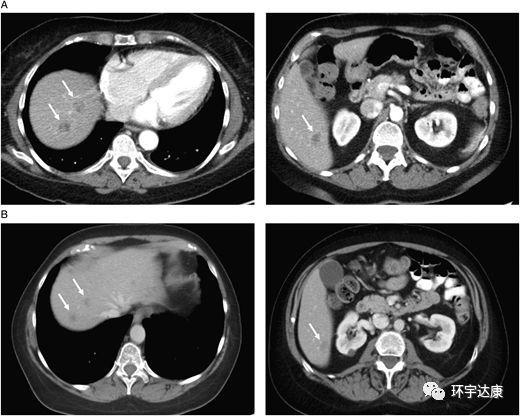

晚期胰腺癌肝转移病灶消失,胰头肿瘤减少50%,基因检测功不可没 胰腺癌

胰腺癌晚期胰腺癌肝转移病灶消失,胰头肿瘤减少50%,基因检测功不可没

2013年11月,一位62岁的美国男性因体重减轻与无痛性黄疸诊治,无用药史。胸部的CT扫描,腹部和骨盆检查发现肝脏肿块和假定胰腺肿块。他接受了内镜逆行胰胆管造影(ERCP)和置入金属支架,症状明显改善。之后,CT引导下肝肿块穿刺活检。病理学检查中度分化腺癌,源于原发性胰腺。患者接受吉西他滨和厄洛替尼,病情稳定两个月,因副作用而停药。病人持续性疲乏、体重减轻

在2015年秋天,44岁的年轻人Doron Broman被诊断患有胰腺癌 - 并且惊讶地发现他的胰腺癌已经转移到肝脏上一个大肿瘤。 医生曾断言,他只有几个月的生存期,而两年后,Doron Broman的影像学检查显示,肿瘤已经奇迹般全部消失了!也许这在过去纯属天方夜谭,而在精准医疗迅速发展的今天,一切皆有可能。  胰腺癌一直被公认为“癌症之王”,对于这种预